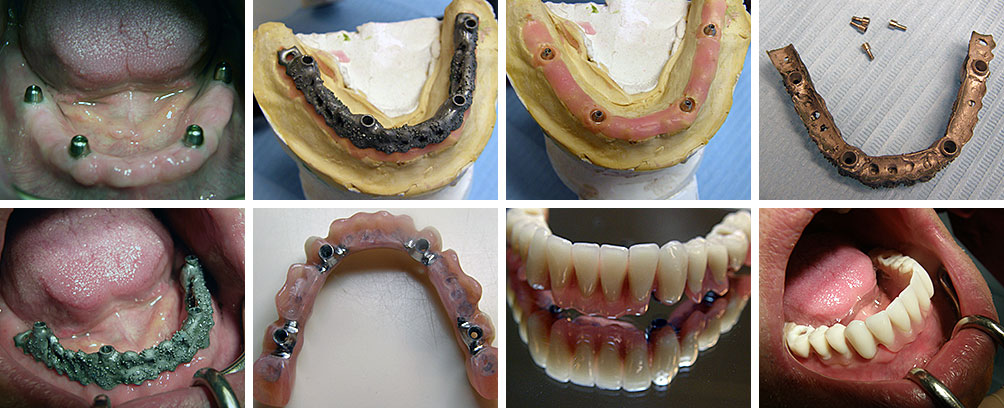

Implantologija